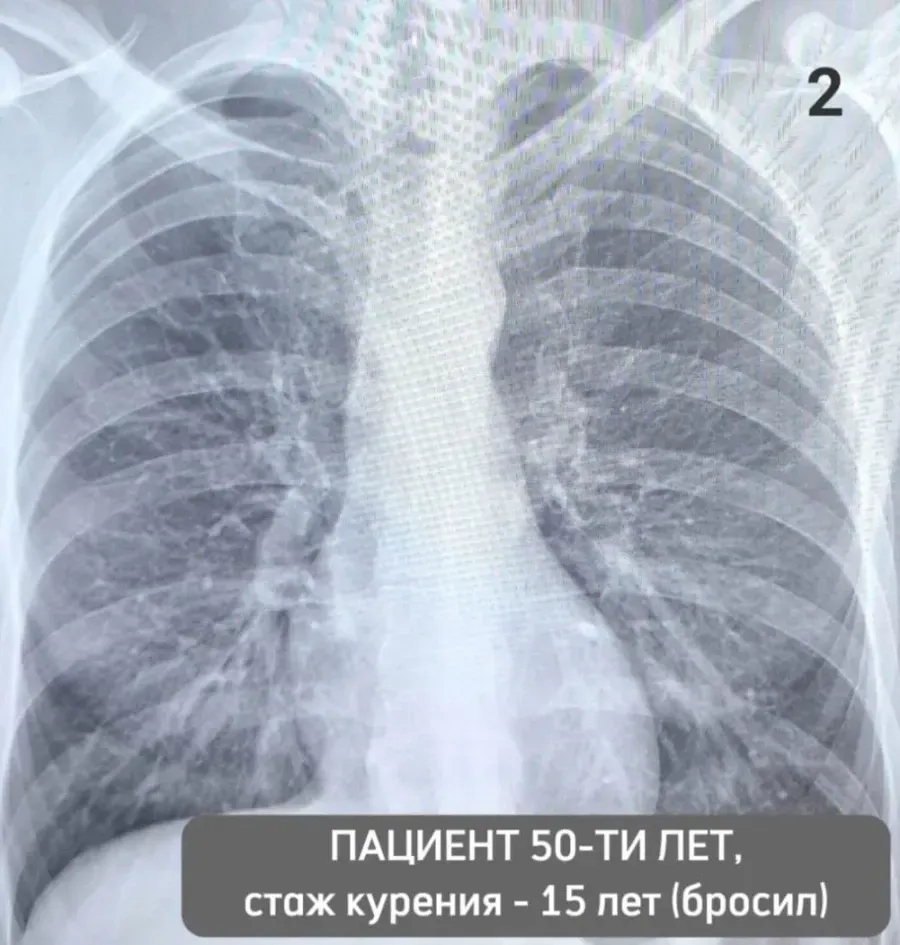

Рентгеновские снимки при пневмоцистной пневмонии